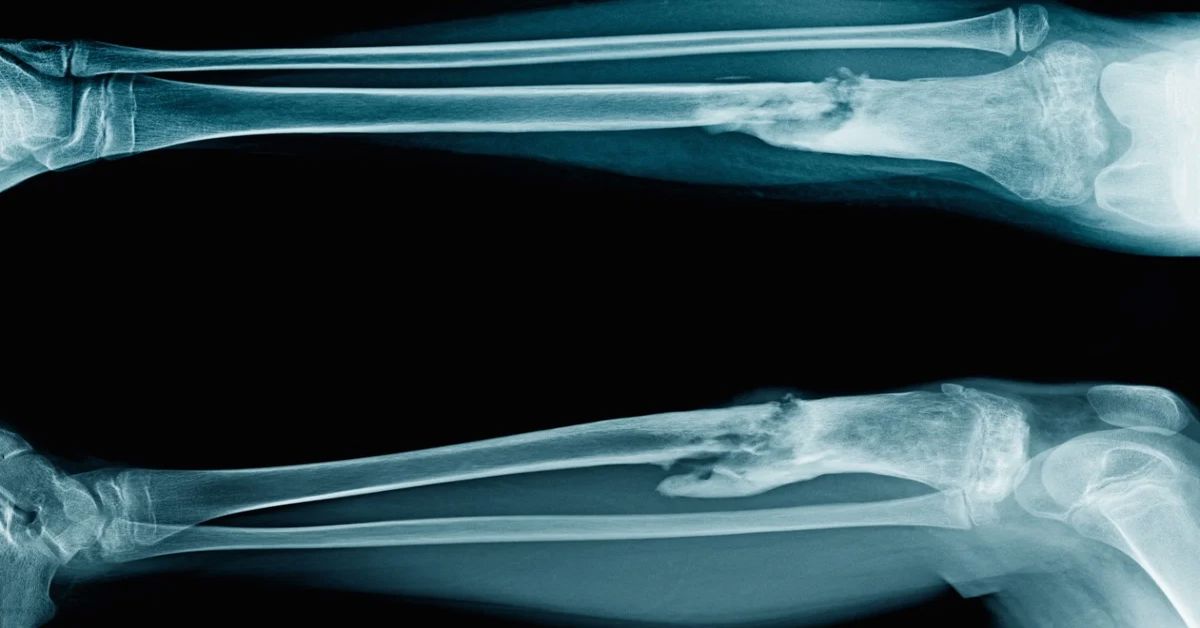

Osteomiyelit, bakterilerin veya nadiren mantarların kemiğe yerleşmesiyle oluşur. Bu durum, kemiğin iltihaplanmasına neden olan bir enfeksiyon türüdür. Genellikle açık yaralar, ameliyat sonrası komplikasyonlar sonucu gelişebilir. Vücutta bulunan başka bir enfeksiyonun kana karışması da bu duruma yol açabilir. Kemik enfeksiyonu tedavisi, enfeksiyonun şiddetine ve süresine göre planlanır. Hastanın genel sağlık durumu da tedavi sürecinde önemli bir rol oynar.

Açık kırık geçiren hastalarda enfeksiyon riski artar. Cerrahi operasyon sonrası yara iyileşmesi yavaş olan veya protez takılan kişilerde de bu risk yüksektir. Bu kişilerde enfeksiyonun erken dönemde tespit edilmesi önemlidir. Tedavinin hızlı başlatılması, kemiğin zarar görmesini önlemeye yardımcı olur.

Açık kırıklar, kemik cerrahisi sonrası komplikasyonlar riskini artırır. Ayrıca protez uygulamaları sonrasında da enfeksiyon olasılığı yükselir. Bu tür durumlarda enfeksiyon hızla kemiğe yerleşebilir. Tedavi edilmezse kemik dokusunda kalıcı hasarlara yol açabilir. Diyabet, damar tıkanıklığı ve kronik böbrek hastalığı gibi altta yatan sağlık sorunları olan bireylerde iyileşme süreci yavaşlar. Bu durum enfeksiyon riskini de artırır.

Bazı durumlarda kemik enfeksiyonu tedavisi cerrahi müdahale gerektirebilir. Enfekte bölgenin temizlenmesi, ölü dokuların çıkarılması veya iltihabın boşaltılması cerrahi yöntemle yapılır. Cerrahi tedavi, özellikle enfeksiyonun ilerlediği durumlarda önem kazanır. Ayrıca kemik dokusunun zarar gördüğü ve enfeksiyonun kronikleştiği vakalarda da uygulanır.